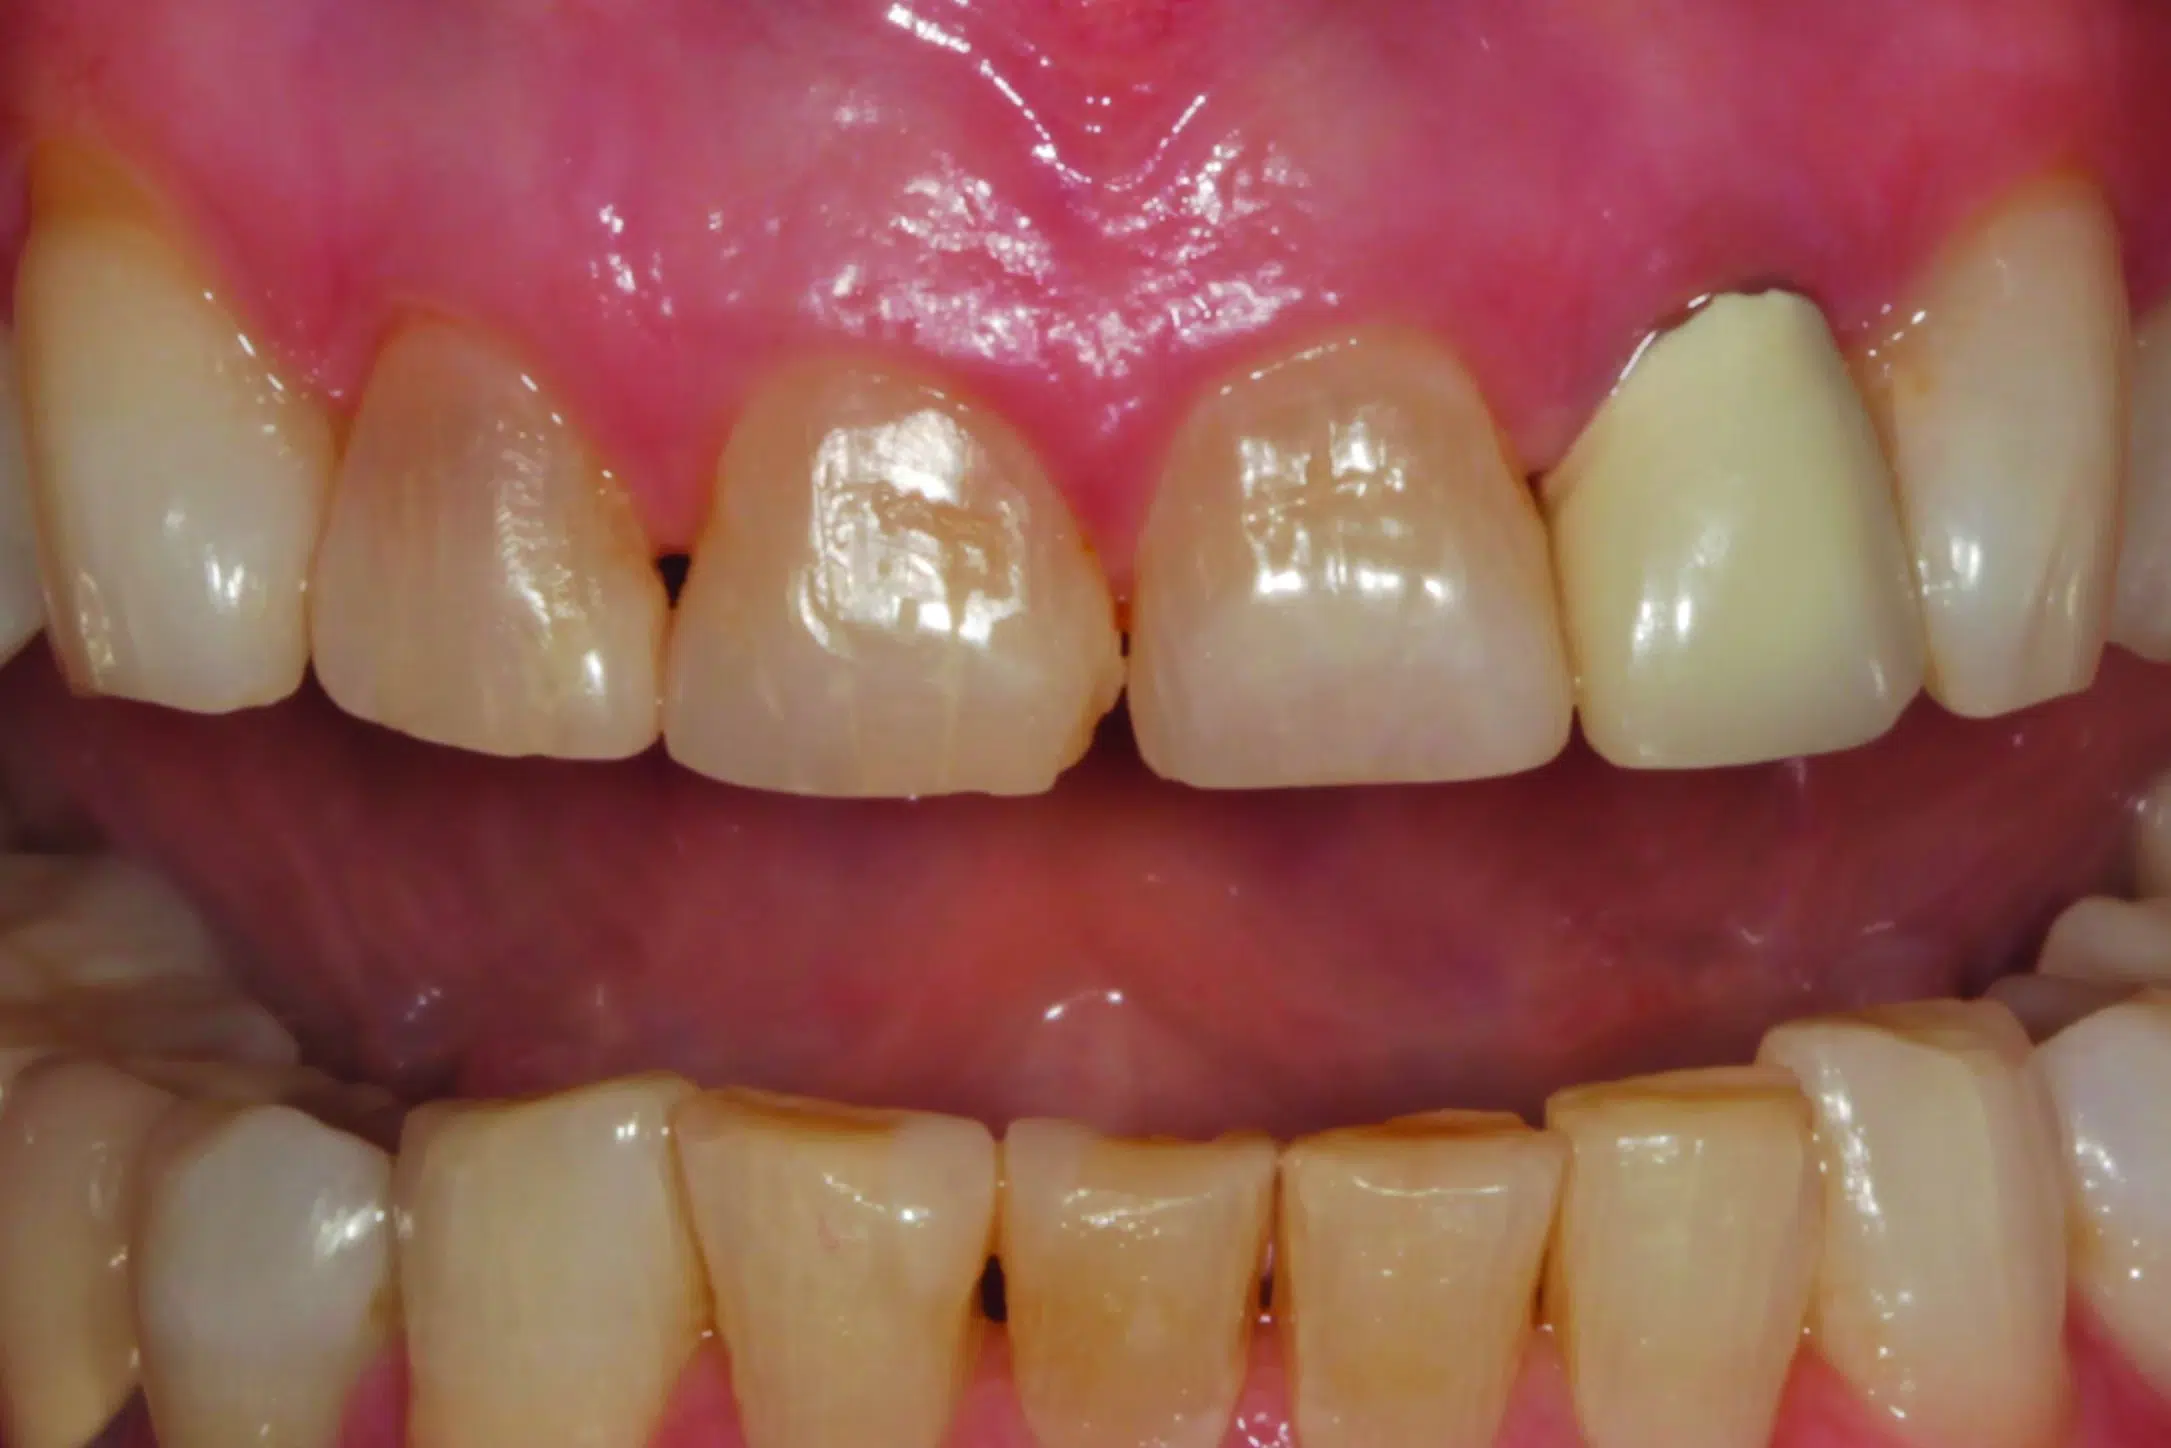

En, sedan många år tillbaka, kvinnlig patient, nu i tidig 70-års ålder kom till praktiken, missnöjd med oestetisk färg och form på tand nr 22 (bild 1). Många år tidigare hade tanden blivit endodontiskt behandlad. En metallpelare hade cementerats för att bygga upp och stärka tanden inför en metallkeramisk krona (bild 2), som utformades så att den skulle maskera stiftets färg. Vid undersökningen påtalade tandläkaren att den mesiala ytan på tand 11 hade flisats av. Han föreslog att den tanden också skulle behandlas, tillsammans med missfärgningarna på tänderna 12 och 21 (bild 3). Den rekommenderade behandlingsplanen innebar att förse tänderna 11-13 och 21-23 med helkeramiska restaurationer. Efter att patienten hade gått med på behandlingsförslaget och innan behandlingen satte i gång, tog tandläkaren en serie extra- och intraorala bilder för kommunikationen med det tandtekniska laboratoriet. Vid behandlingstillfället bedövades patienten och kronan på 22 togs bort och tänderna 11-13 och 21- 23 preparerades för helanatomiska kronor. För att kommunicera pelarfärgen till laboratoriet, fotograferades preparationerna med ett färgprov (IPS Natural Die Material Shade Guide ND7, Ivoclar) (bild 4) och skannades digitalt (Trios 4, 3Shape). Temporära restaurationer framställdes med en prefabricerad skena som hade tillverkats efter starttillfällets diagnostiska design (PerfecTemp II, DenMat).

- (3.) Intraoral närbild med lätt öppen mun och tänderna isär. Flisa och missfärgning på tand 11 och missfärgningar på 12 och 21. Den rekommenderade behandlingsplanen var att restaurera tänderna 11-13 och 21-23 med helkeramiska kronor.